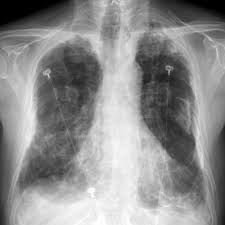

A full time gp is likely to diagnose approximately one person with lung cancer each year. asbestosis may be diagnosed through a ct scan and listening to the lungs. Over 43,000 new lung cancers are diagnosed each year in the uk. Symptoms of pleural mesothelioma include: asbestosis, lung cancer, and mesothelioma.pleural plaques are the most common manifestation of exposure. An ilo of 2/1 or greater; mesothelioma cancer involves the formation of tumors within the lining of the lungs, abdomen or heart and is treated similarly to lung cancer, often with chemotherapy and radiation. Less commonly the lining of the abdomen and rarely the sac surrounding the heart, or the sac surrounding the testis may be affected.

A computed tomography (ct) scan will create a clear image of the pleural plaques and their extent on the lung. Emphysema is caused when the alveoli in the lungs become damaged. asbestosis is one of many types of pulmonary fibrosis. The spectrum of manifestations on ct in 70 cases. After several years, the inhalation of these fibers can lead to irritation and scarring in the lungs and shortness of breath, among other symptoms. Pleural mesothelioma is the only known pleural cancer and is caused by asbestos exposure in nearly all cases. The cancer can spread to other parts of the body as it progresses. Malignant mesothelioma is a type of cancer that typically develops in the pleura (the lining of the lungs). Signs and symptoms of mesothelioma may. Grosh, ivid, and ward m. cxrs are taken to have a look at abnormalities within the lung like thickening of the pleura or nodules within the lungs. Pleural plaques are deposits of fibrous tissue that develop in the chest cavity as a result of asbestos exposure. Although the use of asbestos and asbestos products has dramatically decreased in recent years, they are still found in many residential and commercial settings and continue to pose a health.

mesothelioma is a cancer which affects the lining of the lungs (pleura) and the lining surrounding the lower digestive tract (peritoneum) mesothelioma cxr. It can take between 20 and 50 years for pleural mesothelioma to present itself after asbestos exposure.